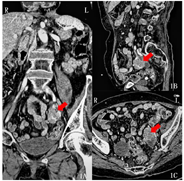

入院体格检查:神志清楚,言语清晰流利,悬雍垂居中,双侧软腭抬举可,咽反射存在,余颅神经检查正常。双上肢肌萎缩,双上肢近端肌力2级、远端1级,双下肢肌力4级,四肢肌张力低,双侧肘关节以下针刺痛觉减退,双膝关节以下针刺痛觉、震动觉、位置觉减退,双侧指鼻试验、轮替试验不能完成,跟-膝-胫试验尚可,四肢腱反射未引出,双侧Babinski征阴性。血尿便常规、肝肾功能、电解质、凝血功能、病毒系列、血管炎抗体、抗干燥综合征A型和B型抗体、血清免疫固定电泳未见明显异常。血清维生素B12 1 446 pg/ml(参考180~914 pg/ml),抗核抗体1∶1000,肿瘤标志物:糖类抗原125 4 053 U/ml(参考0~35 U/ml),人附睾蛋白4 293 pmol/L(参考0~140 pmol/L),糖类抗原724 11.5 U/ml(参考0~6.9 U/ml)。血清抗Yo抗体阳性,神经节苷酯抗GM1、GD1a、GD1b、GD2抗体阳性。腰穿脑脊液清亮、透明,压力正常,有核细胞计数13×106/L,单个核细胞为主(10×106/L),蛋白0.57g/L(参考0.15~0.45 g/L),葡萄糖和氯化物正常,脑脊液细胞学:可见少量成熟淋巴细胞、单核细胞。肌电图:多发周围神经受损(双侧基本对称,上肢重,累及运动、感觉纤维,轴索损害与脱髓鞘并存,以轴索损害为主,下肢以感觉纤维为主)。运动、感觉神经传导速度结果见表1、表2。F波:双胫神经F波出现率及潜伏期正常。针极肌电图:右第一骨间肌、肱二头肌及左拇短展肌可见纤颤电位和正锐波,右肱二头肌运动单位电位时限延长,右第一骨间肌、左拇短展肌主动收缩无运动单位电位,余所检肌募集电位减少。全腹盆腔增强CT:左侧附件区囊实性肿块,考虑卵巢癌;腹盆腔及腹膜后多发增大淋巴结,考虑转移(图1)。妇科会诊,考虑卵巢癌可能性大,建议进行B超引导下穿刺活检,转妇科行手术治疗。患者及家属要求出院,未行活检及手术治疗。